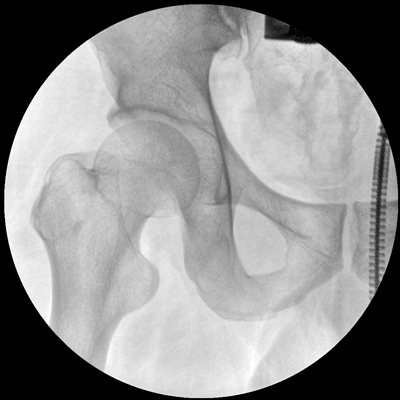

Clinical picture

臨床圖片